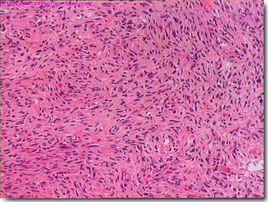

2.5 病理組織檢查確診。